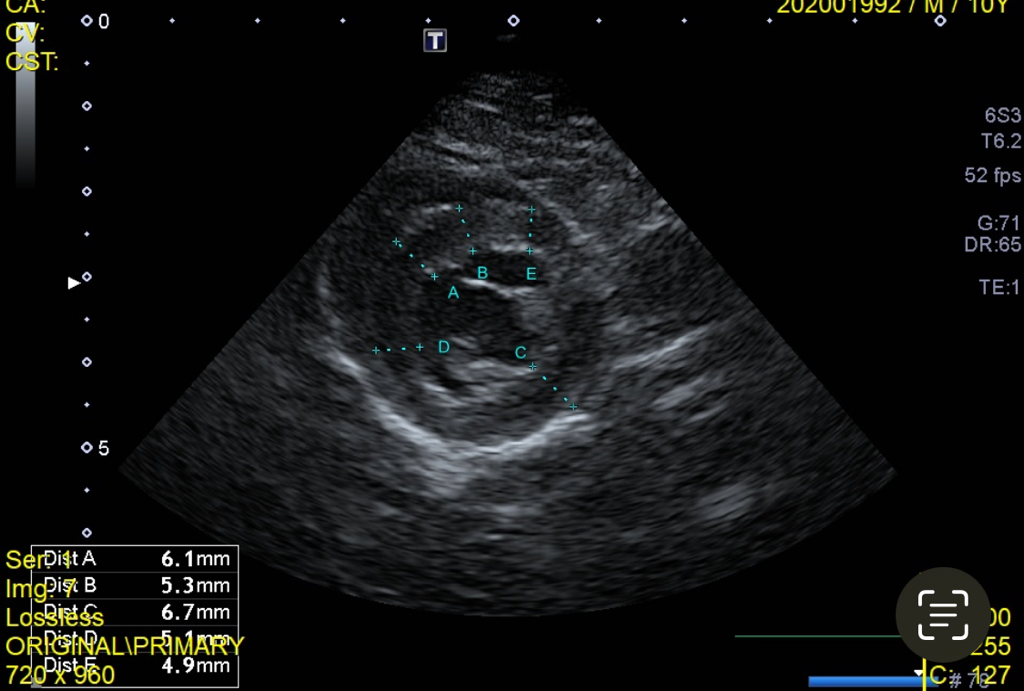

12살 7.7kg 고양이 신부전때문에 검사하고 정상수치 된 후 혹시 몰라 심장 초음파랑 pro 검사 같이했는데요 7월 처음 초음파 검진시 가장 얇은 두께 4.9mm 두꺼운건 6.7mm 였고 NT-pro 수치가 400후반대라 심장병 b1 단계로, 약먹을정도 정도는 아니라해서 3개월 후에 보기로 한 후